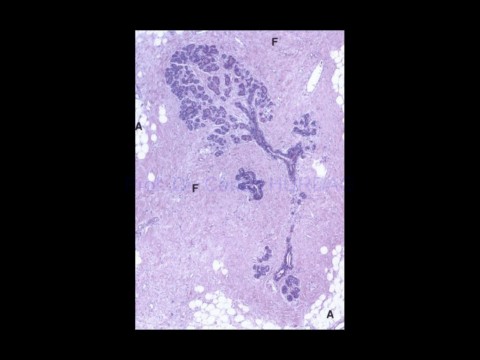

Page 97 - KADIN ÜREME SİSTEMİ

Prof. Dr. Canan HURDAG